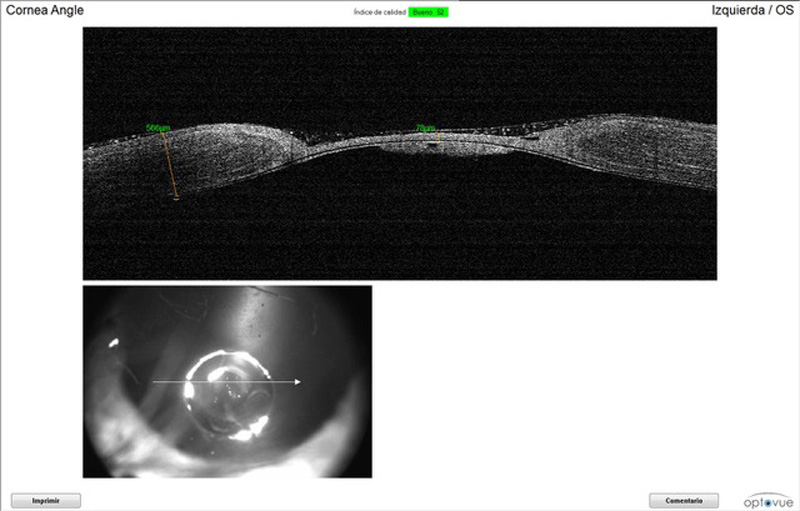

OCT del segmento anterior

Realizaremos este tipo de OCT cuando necesitemos:

- Medir el espesor de la córnea. Útil en casos de úlceras corneales profundas, degeneraciones de córnea etc.

- Ver alteraciones en la estructura de la córnea: depósitos lipídicos, secuestro corneal, edema en la córnea, bullas epiteliales.

- Valorar al ángulo iridicorneal, importante en pacientes con glaucoma

- Valorar la profundidad de la cámara anterior